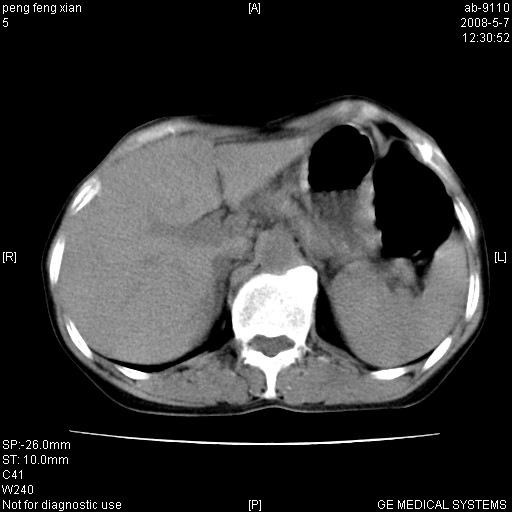

女,56岁。b超左一腹包块,考虑胃肠道肿瘤。

胃壁增厚,左前胸壁局限性隆起,考虑胃癌可能性大,建议做胃镜

典型胃癌胰体尾部受侵。

胃体部胃壁增厚,不均匀性强化,与胰腺分解欠情.

考虑:胃癌,胰腺受侵待除外.

鉴别:胃淋巴瘤(强化不明显)

建议:胃镜检查.